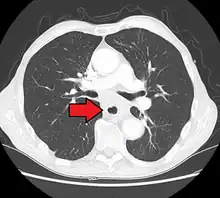

Additional testing is needed to assess how much the cancer has spread (see #Staging, below). Computed tomography (CT) of the chest, abdomen and pelvis can evaluate whether the cancer has spread to adjacent tissues or distant organs (especially liver and lymph nodes). The sensitivity of a CT scan is limited by its ability to detect masses (e.g. enlarged lymph nodes or involved organs) generally larger than 1 cm.[41][42] Positron emission tomography is also used to estimate the extent of the disease and is regarded as more precise than CT alone.[43] Esophageal endoscopic ultrasound can provide staging information regarding the level of tumor invasion, and possible spread to regional lymph nodes.

Contrast CT scan showing an esophageal tumor (axial view)

Contrast CT scan showing an esophageal tumor (coronal view)